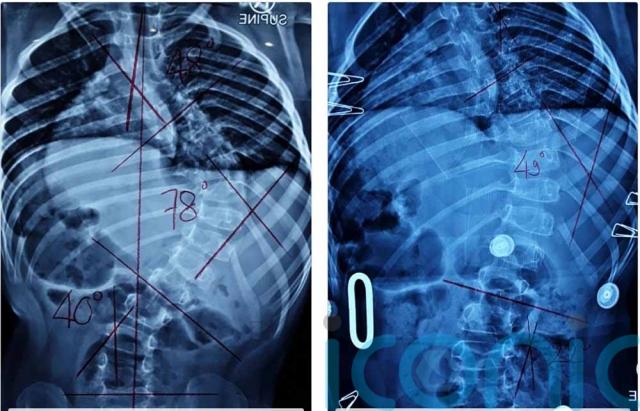

Since his scoliosis diagnosis in 2015, the curve of his spine has gone from 18 degrees to 90 degrees, meaning surgery is now essential.

Twone said: “His spine has rotated and has twisted his rib cage. I am worried his nerves are trapped because of how curved it is.

Fearing that  his spine could soon curve into his body and crush his internal organs, the family have been told that a procedure called posterior spinal correction, with instrumented fusion ideally, is essential in the early part of this year.

If Kai has a growth spurt at puberty, his spine will curve too much for it to be possible.